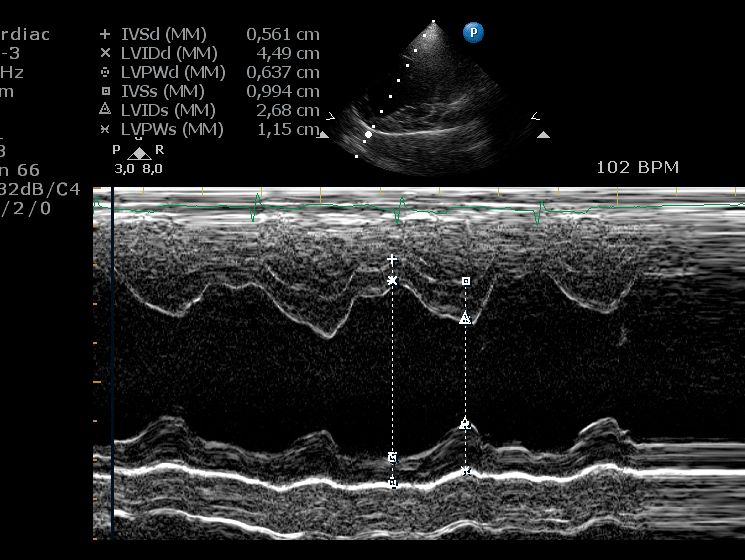

echocardiogram bij een hond. - M-mode echografie – Dit geeft een eendimensionaal beeld waarmee we nauwkeurig de dikte van de hartwand en de grootte van de kamers tijdens samentrekking en ontspanning meten. Deze techniek wordt veel gebruikt bij het opsporen van hartaandoeningen zoals dilaterende cardiomyopathie (DCM) bij honden en hypertrofische cardiomyopathie (HCM) bij katten.